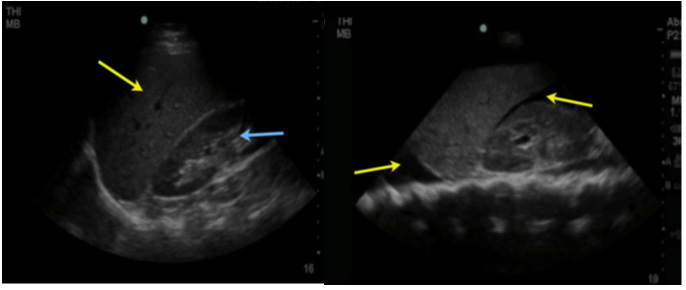

Upper left quadrant

Fluid can collect in the space between the spleen and the left kidney, the splenorenal flexure, similarly to the right side, settling between the 2 organs. Its exploration is similar to that of the right side, except for the higher and posterior location of the left kidney due to the little displacement produced by the spleen, for this reason visualization is more difficult due to the acoustic shadows produced by the ribs and requires that the evaluation be performed during the patient's inspiration, without forgetting that the transducer must be in a more posterior position (Figure 5 A and B). A complete evaluation should include the space between the spleen and the left kidney in its entirety to look for free fluid. Contrary to the evaluation of the right side, it is very common for the fluid to be located between the spleen and the diaphragm, so this area should also be examined.

Splenic renal fossa; examination with a low-frequency transducer with a cephalad marker: it allows us to observe: splenic renal fossa and infradiaphragmatic space.

Figure 5A.                                           Figure 5B.

Figure 5A Free renal splenic space (light blue arrow: left kidney, yellow

arrow spleen; 5B. Anechoic image in (yellow arrow) corresponding to intraabdominal

free fluid.

Damage to the spleen can also be detected and appear similar to damage to the liver.

Fluid in the pleural cavity can also be seen in the left lung base, and will be seen as a hypoechoic area over the spleen and diaphragm.